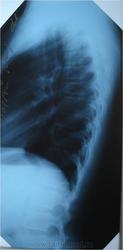

На Кальве не тянет. Костная структура позвонка не изменена. Это может быть проекционное искожение. T8 находится как раз на вершине сколиотической дуги.

На Кальве не тянет. Костная структура позвонка не изменена. Это может быть проекционное искажение. T8 находится как раз на вершине сколиотической дуги.

Трапецевидную форму тел позвонков на уроне Th6-Th8-можно рассматривать как вариант нормы(из лекций профессора Жаркова П.Л.).

На снимке, уважаемый Александр (простите, отчество не знаю), не клиновидная, а трапециевидная деформация позвонка? Хорошо, допустим, норма. Но наличие болевых ощущений в области позвонка измененной формы не должно ли вызвать некоторую настороженность?

Похоже на клиновидную деформацию Тн-8 (снижение высоты в переднем отделе тела позвонка ) -компресия.

Посттравматическая деформация D8 в исходе его компрессионного перелома?